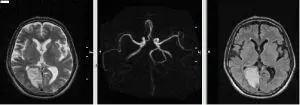

При проведенні МРТ на сучасному обладнанні видно навіть незначні зміни в мозку, пов’язані з порушенням мозкового кровотоку. Сучасне МРТ обладнання дозволяє бачити мінімальні зміни в ішемічному мозку, які тільки починають розвиваються на ранніх стадіях зниження кровотоку мозку.

Чітко видно інсульт (див. Нижче).